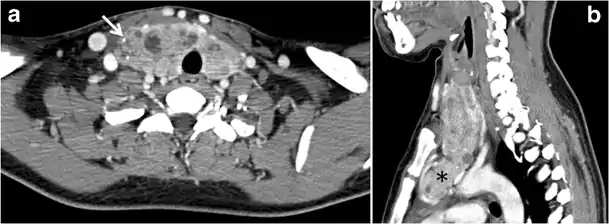

Malignancy can coexist within the goiter and a CT scan may give a clue if there are abnormal cervical lymph nodes and/or signs of invasion. Retrosternal extension (Fig. 15) could affect the surgical approach, as a lower extent may require a partial or total sternotomy to facilitate complete resection. Therefore, the distance of the retrosternal extent from the sternal notch should be measured on a sagittal image.[1]

The interpreting radiologist should describe the mass effect, detailing its degree and direction of displacement of central structures, including the trachea, oesophagus, larynx, and pharynx. Attention should be directed to the upper extent of the goiter and structures immediately surrounding the thyroid gland, including the neuro-vascular structures, retropharyngeal space, and pre-vertebral space. The reporting radiologist should evaluate the vocal cords for symmetry and signs of vocal cord palsy.[1]